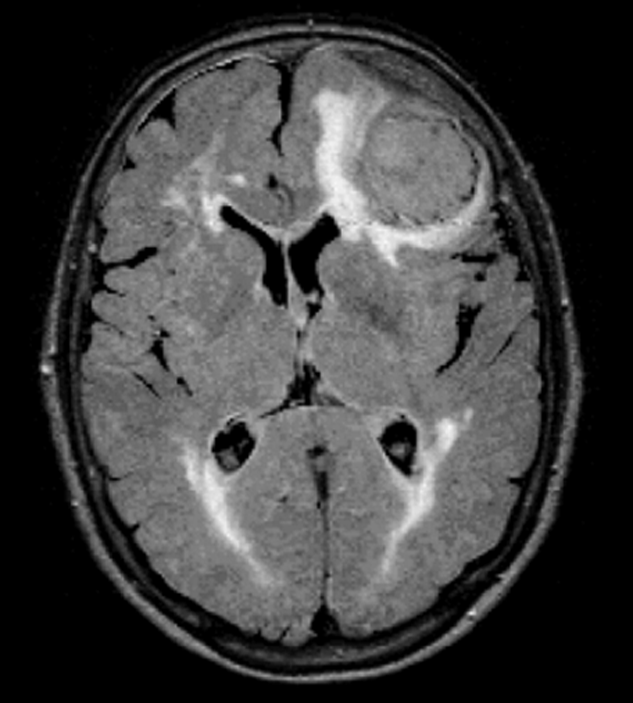

Figure 10-11:

FLAIR. TR = 8000 ms, TE = 120 ms, TI = 2000 ms. The brain lesions caused by the pressure of huge me­nin­gi­oma are well seen on the FLAIR image.

spaceholder redFLAIR (Fluid Attenuated Inversion Recovery) eliminates the signal from ce­­re­­bro­­spi­­nal fluid by using very long inver­sion times (2000–2500 ms). It is espe­ci­al­ly useful in brain lesions with low contrast (Figure 10-11).

CSF reaches the null point of no signal at an inversion time of ~2000 ms (TR > 8000 ms; TE > 100 ms), depending on field strength  [⇒ De Coene 1992].